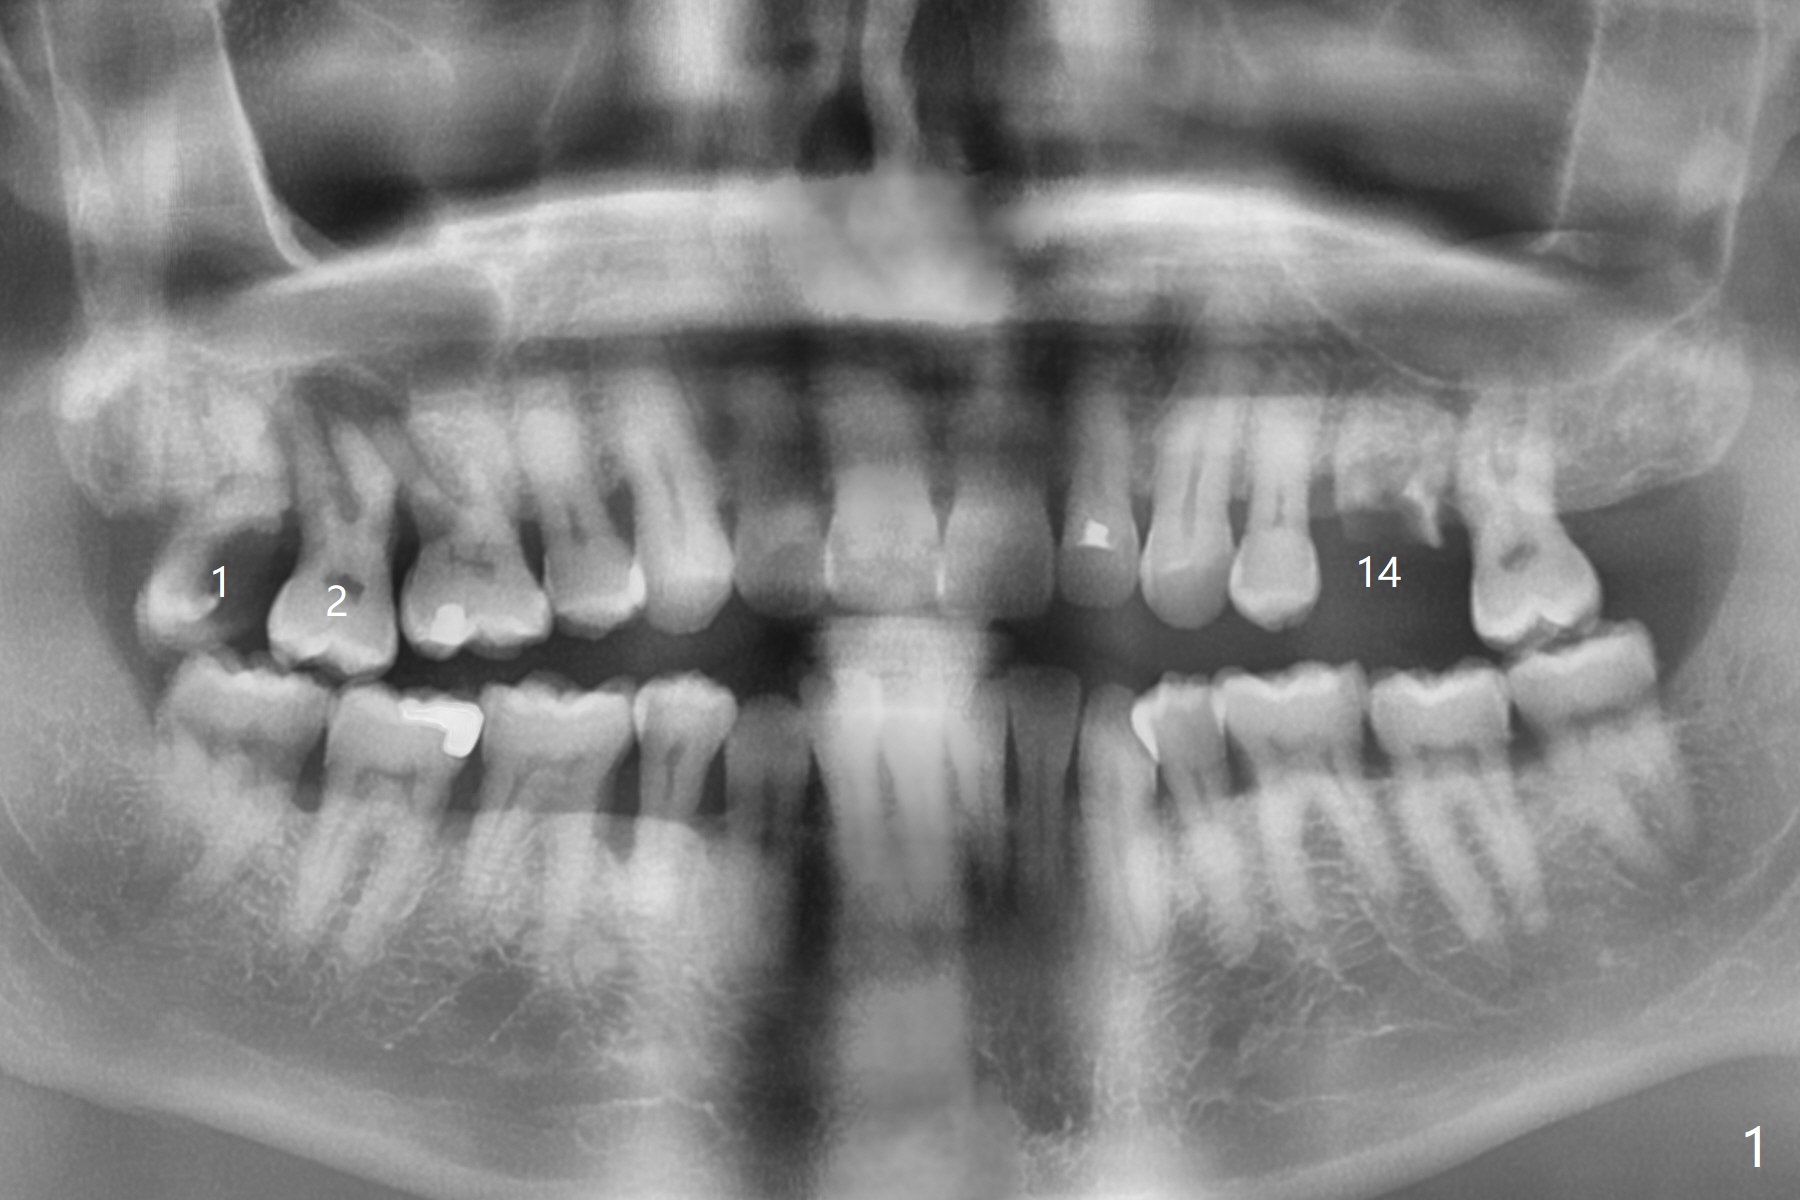

A 55-year-old man agrees to have the tooth #1 extraction immediately post SRP. Pre-extraction panoramic X-ray shows severe bone loss at #2 (Fig.1). Possible extraction of #2 is mentioned considering pending implant at #14. Extraction of #1 turns out to be difficult, requiring sectioning. The tooth #2 blocks the access. The patient readily accepts #2 extraction. Removal of abundant granulation tissue at #2 is associated with severe hemorrhage from the Greater Palatine Vessels. After pressure hemostasis, a piece of Osteogen Plug is placed at #1, the other palatal of #2 to control hemorrhage. With hemostasis, Vanilla graft is placed at #2 securely (without being washed out, Fig.2 *), followed by placement of a third Osteogen Plug on the top of the graft. The last surgical challenge is to close these two large wide sockets with 4-0 Chromic gut and PGA. While the socket #1 remains closed, the one at #2 is open 13 days postop (Fig.3). It appears that a stiffer membrane (6-month) should be sutured in place to keep the Osteogen plug underneath in place. The latter seems to be easily fragmented.